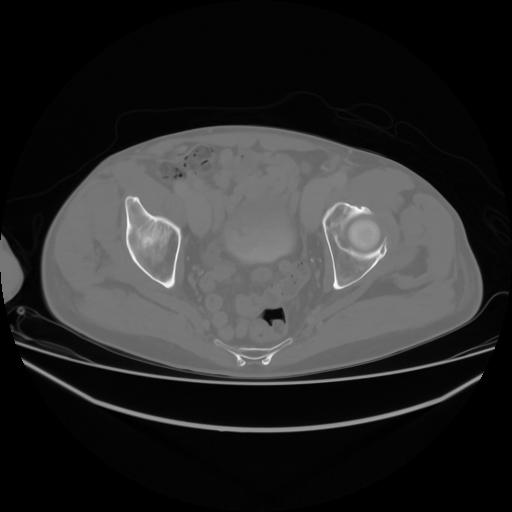

4 CUERPO,CE,Axial,3.0,CUERPO,,